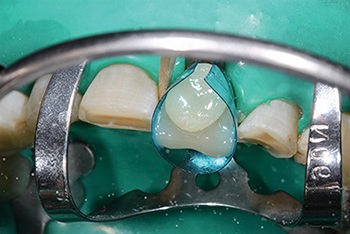

Shaw emphasized the importance of proper isolation for predictable bonding. Using a 90N clamp and rubber dam (Fig. 2), he sandblasted the tooth surfaces before etching to ensure bonding to a clean substrate. Much of the lower incisor work required bonding directly to dentin, making technique and moisture control essential to long-term success.

Fig. 2: Rubber dam isolation